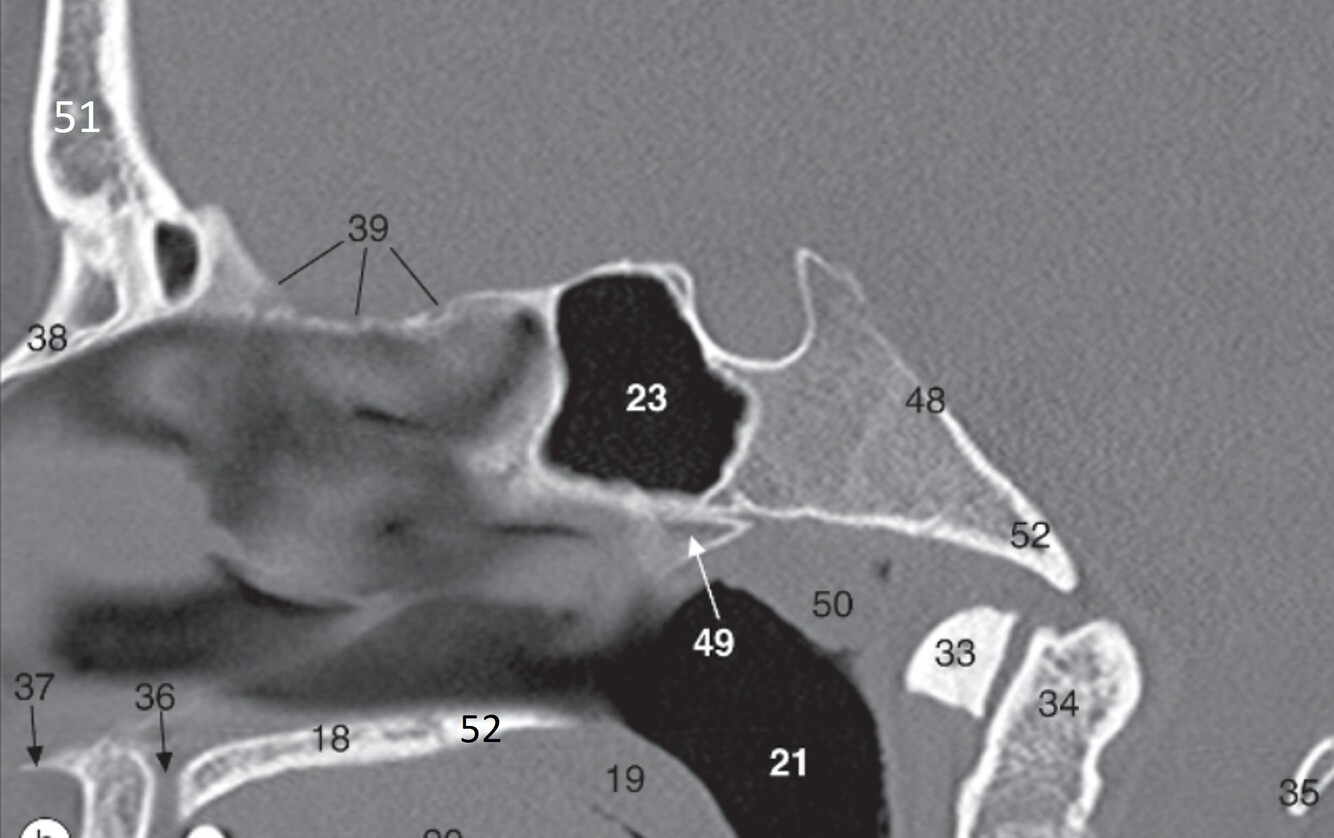

15

Label 18,19,21,23,33,34

A

18=Palatine process (Maxilla)

19=Soft palate

21=Nasopharynx

23=Sphenoid sinus

33=Anterior arch (C1)

34=Odontoid process (C2)

16

Label 35,37,38,39,48

35=Posterior arch (C1)

37=Acanthion

38=Nasal bone

39=Cribriform plate (Ethmoid)

48=Clivus